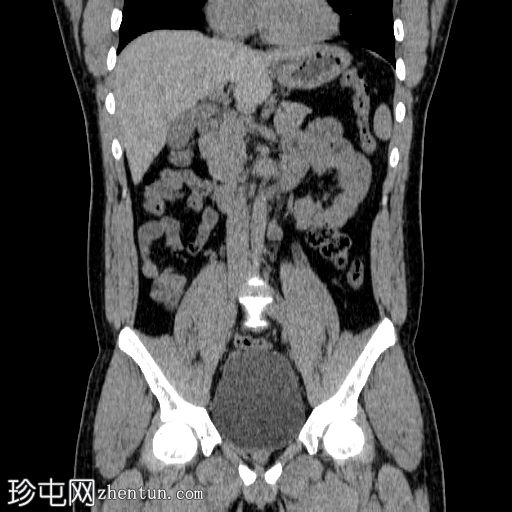

冠状位

平扫

双侧肾结石,无梗阻,较大结石位于左侧肾下盏,最大直径约4 mm,平均CT值约730 HU,伴左侧输尿管轻度扩张。

膀胱明显充盈,高度达脐部,若患者无法排尿,可能需要导尿。